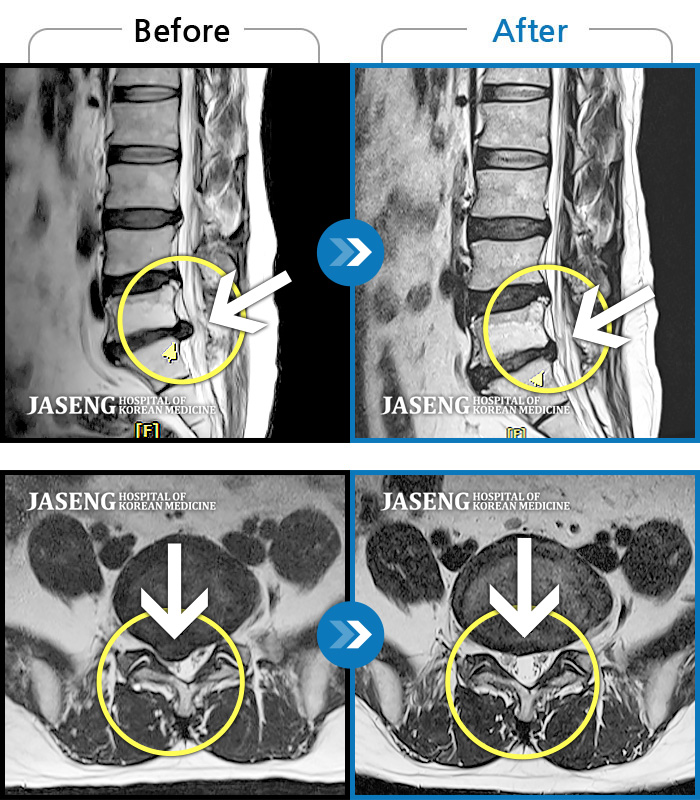

허리디스크

도움받은 사례

광주 · 장영우 원장

양측 허리부터 좌측 다리까지 이어지는 저림과 통증으로 걷기 힘들어 내원하였습니다.

촬영시기

2024.11.22 ~ 2025.05.16

2025.05.30